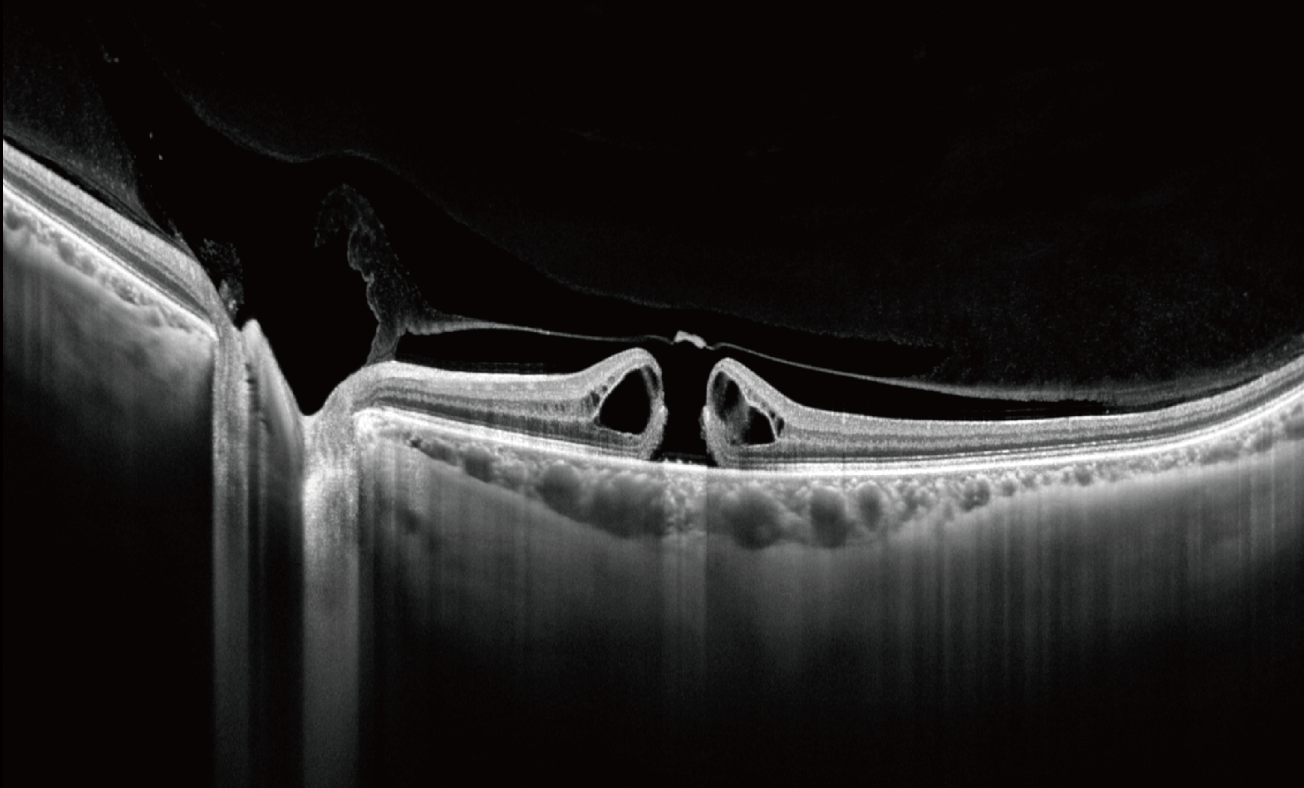

Glaucoma assessment

Anterior & Posterior OCT for full OCT-Based glaucoma Assessment

Use anterior and posterior segment OCT to support 360° angle assessment and comprehensive glaucoma evaluation, while enabling more precise optic disc cupping assessment (horizontal and vertical) than regular examination — helping clinicians document structures and monitor changes with confidence.

Glaucoma

Advanced Glaucoma Screening & Diagnosis

Support glaucoma screening and follow-up with OCT/OCTA structural and vascular evaluation.

Angle assessment

Automated 360° Angle Assessment with Grading

Full angle evaluation with a grading system helps guide management decisions.